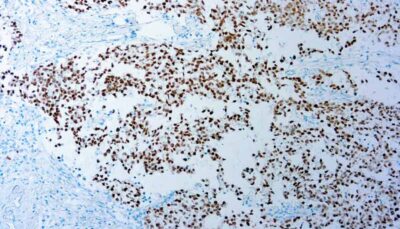

p16 is a tumor suppressor protein that is a cyclin-dependent kinase inhibitor and is essential in regulating the cell cycle. p16 overexpression is a surrogate biomarker of HPV infection (high-risk HPV types), which makes it useful in evaluating HPV-associated squamous and glandular neoplasia of the lower gynecologic trac.